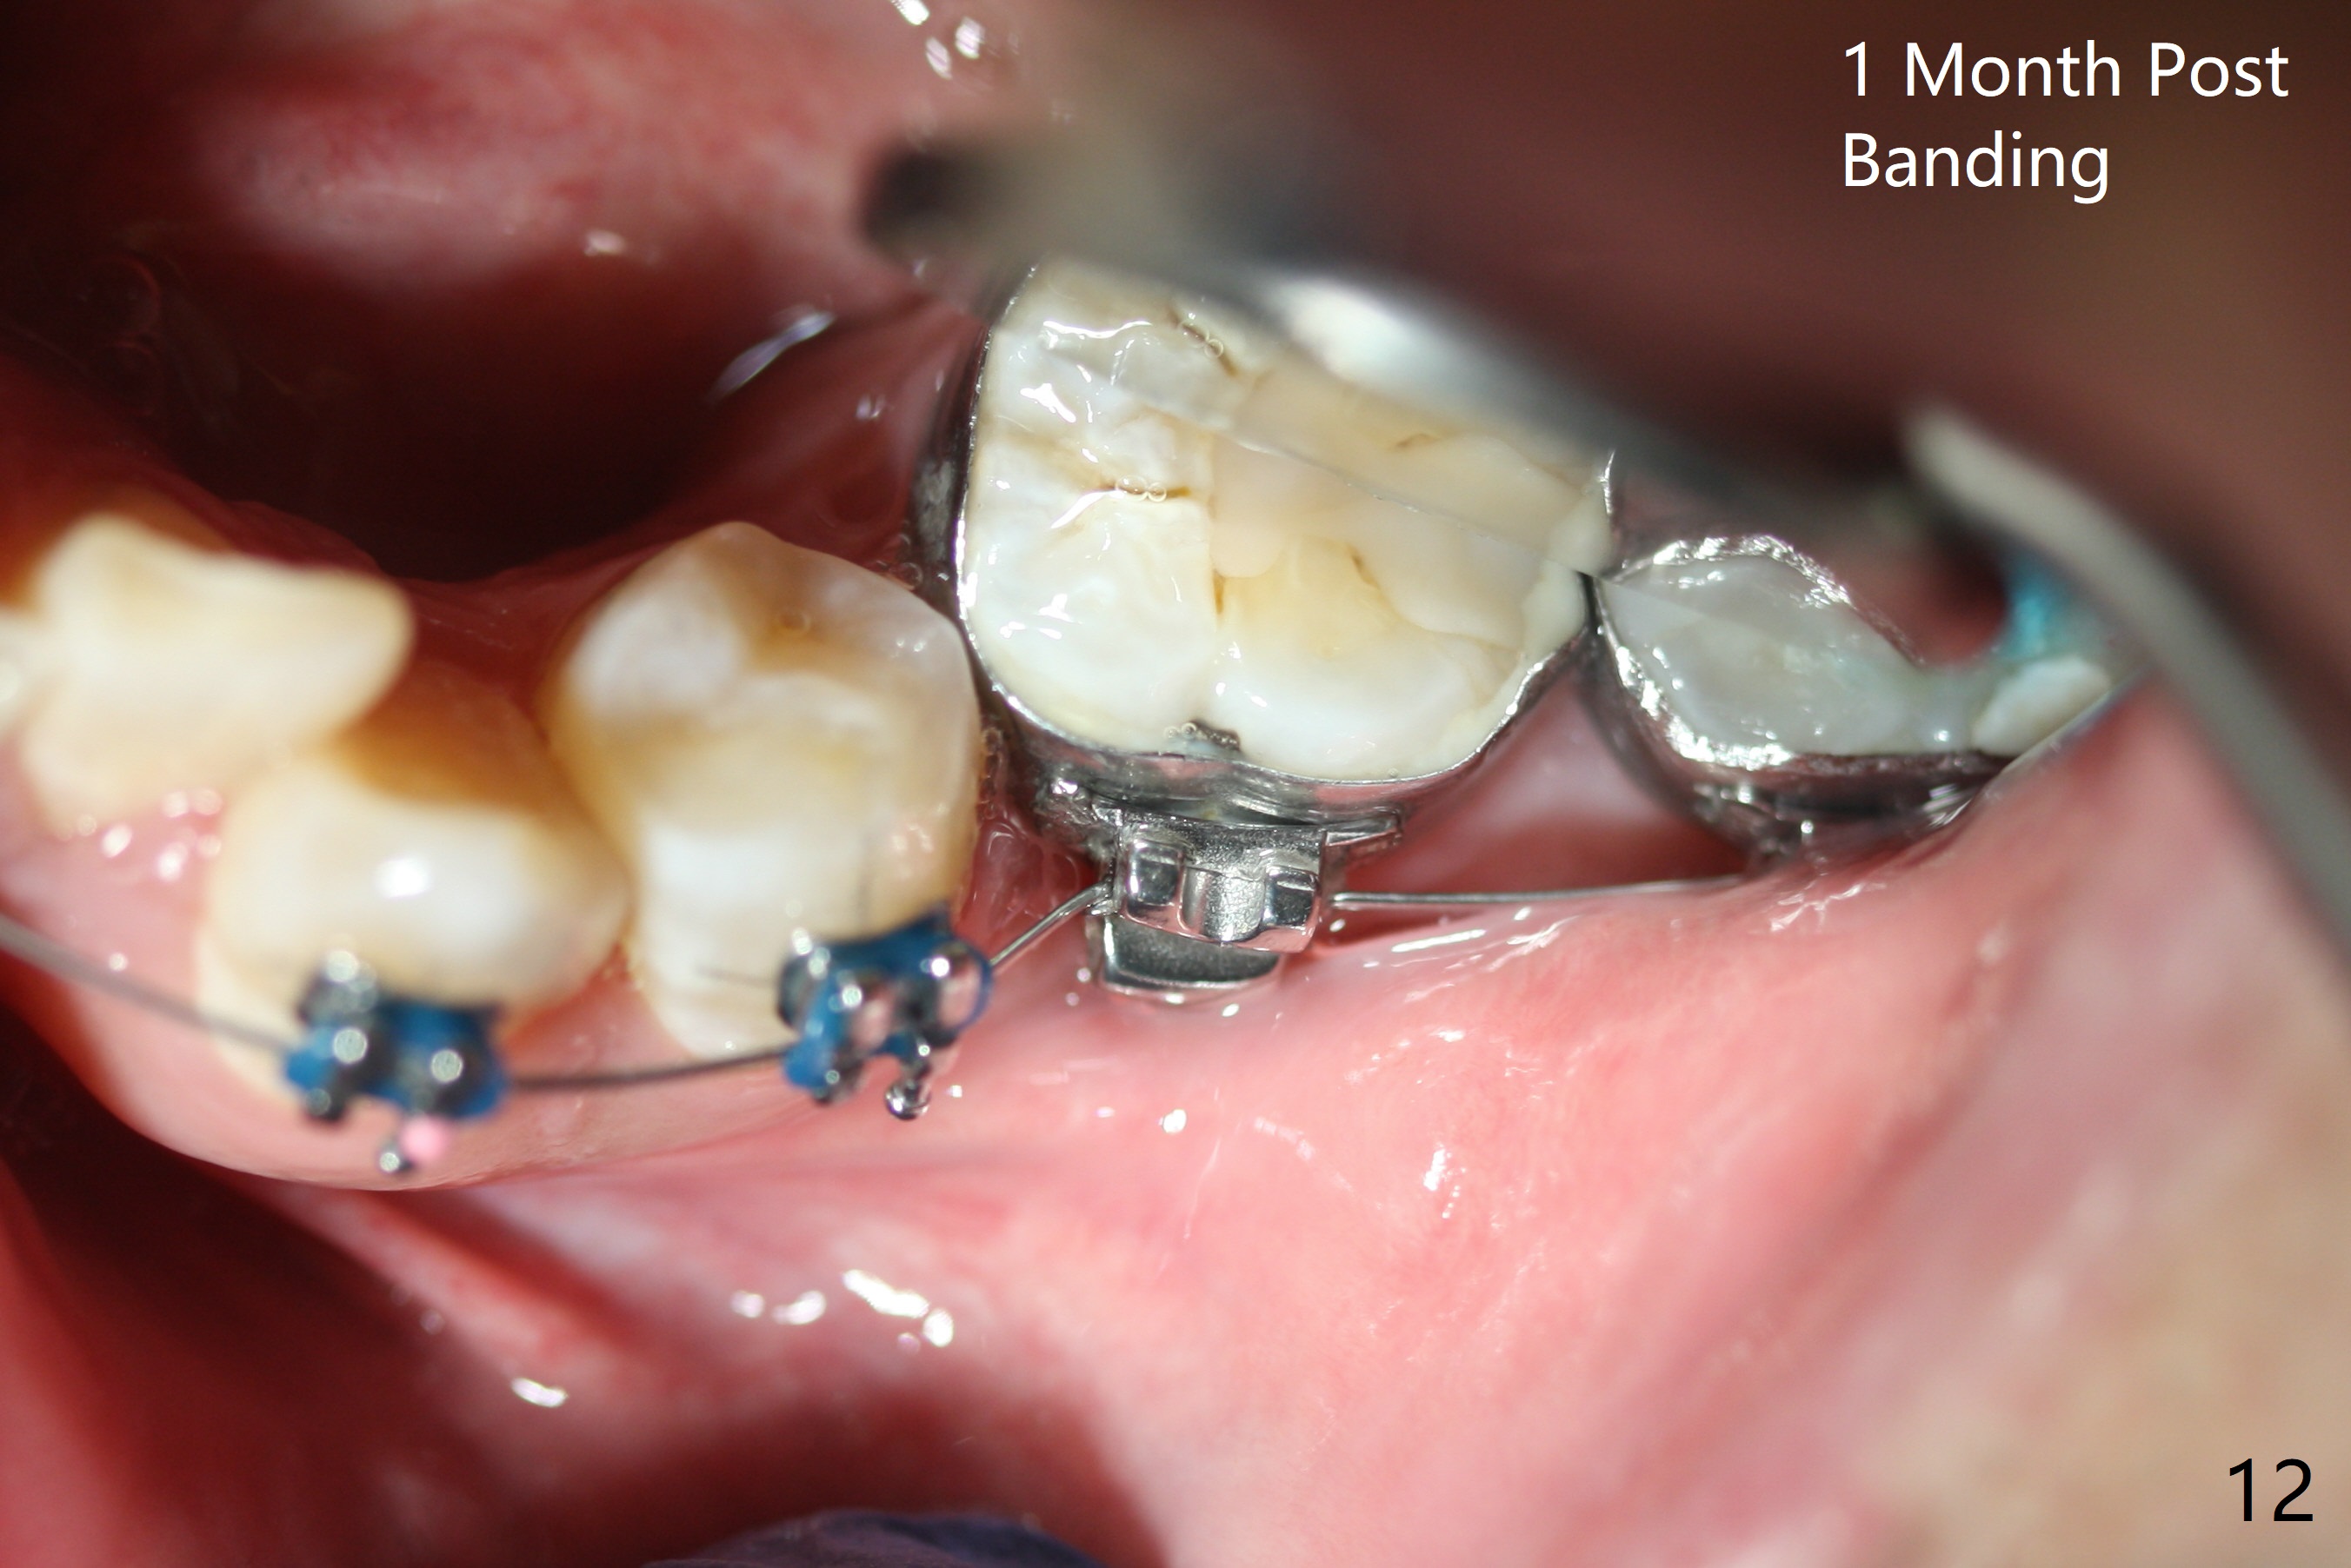

Severe crowding (Fig.1-7) appears to be alleviated especially 2 months after UR5 extraction. Diastemata seem to form mesial and distal to UR2 (Fig.8). Because of severe wear at UR3 (Fig.6), there is no bracket placement differential around it (Fig.8 (14 niti wire)). Lower bands and brackets are placed a week later (Fig.9-11). Because of tight space between LR4 and the opposing tooth (Fig.10), band adhesive is applied to L7 occlusal surface to open the bite (Fig.9). There is an abrupt kink of 12 niti wire between LL4 and 6 (Fig.11). The latter does not improve much in a month; the wires remain the same (Fig.12). For LL2, LR4 has been retracted for ~ 1 month (Fig.13). There is mild tension when 18 ss wire is inserted between LL4 and 6 five point five months post banding (Fig.14). UR4 has been distalized for a month using buccal power chains x3 resulting in rotation; to counter the rotation, a lingual button is placed with power chain x3 lingual and x2 buccal (Fig.15). With space gaining, it is time to finish definitive filling (Fig.16 *). Next visit check midlines, overjet, interdigitation, and molar classification. R4s distalize, but associate with rotation because of power chains buccal and lingual 8 months post banding (Fig.17,18). With the use of the same wires, power chains are applied lingual to continue distalization and rotation correction (Fig.20,21). Lingual buttons are placed at L2s buccalization (Fig.19) and mesialization (Fig.22,23). It appears that space should be created distal to LR3. That is that the lower anterior teeth should be shifted to the right, although it may be not appropriate for the midline.